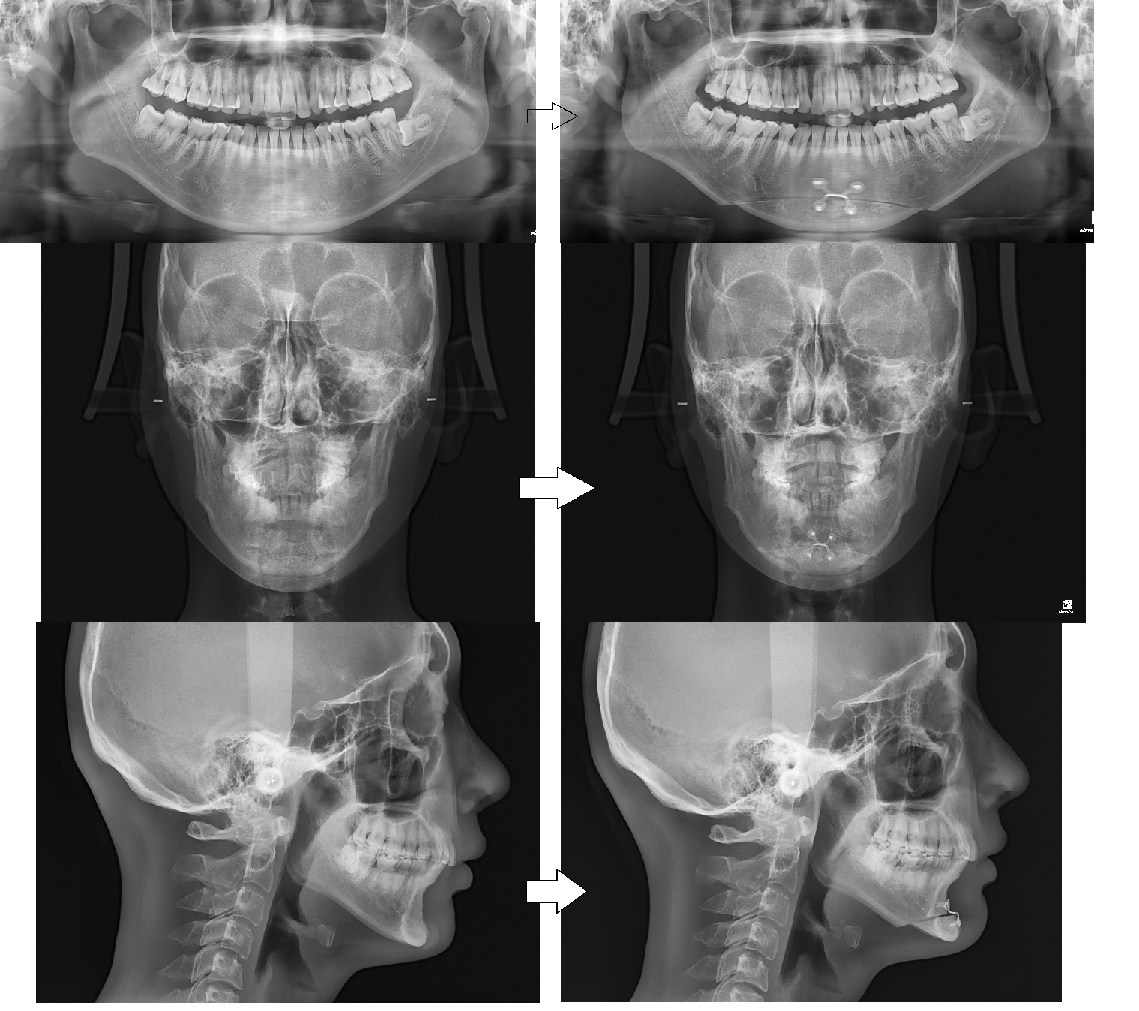

[X-ray 사진]

좌측사진이 무턱보형물을 넣었을 때의 사진이고,

우측사진은 무턱보형물을 빼고 턱끝전진술을 수술한지 3주째의 사진입니다.

현재는 6주차입니다.